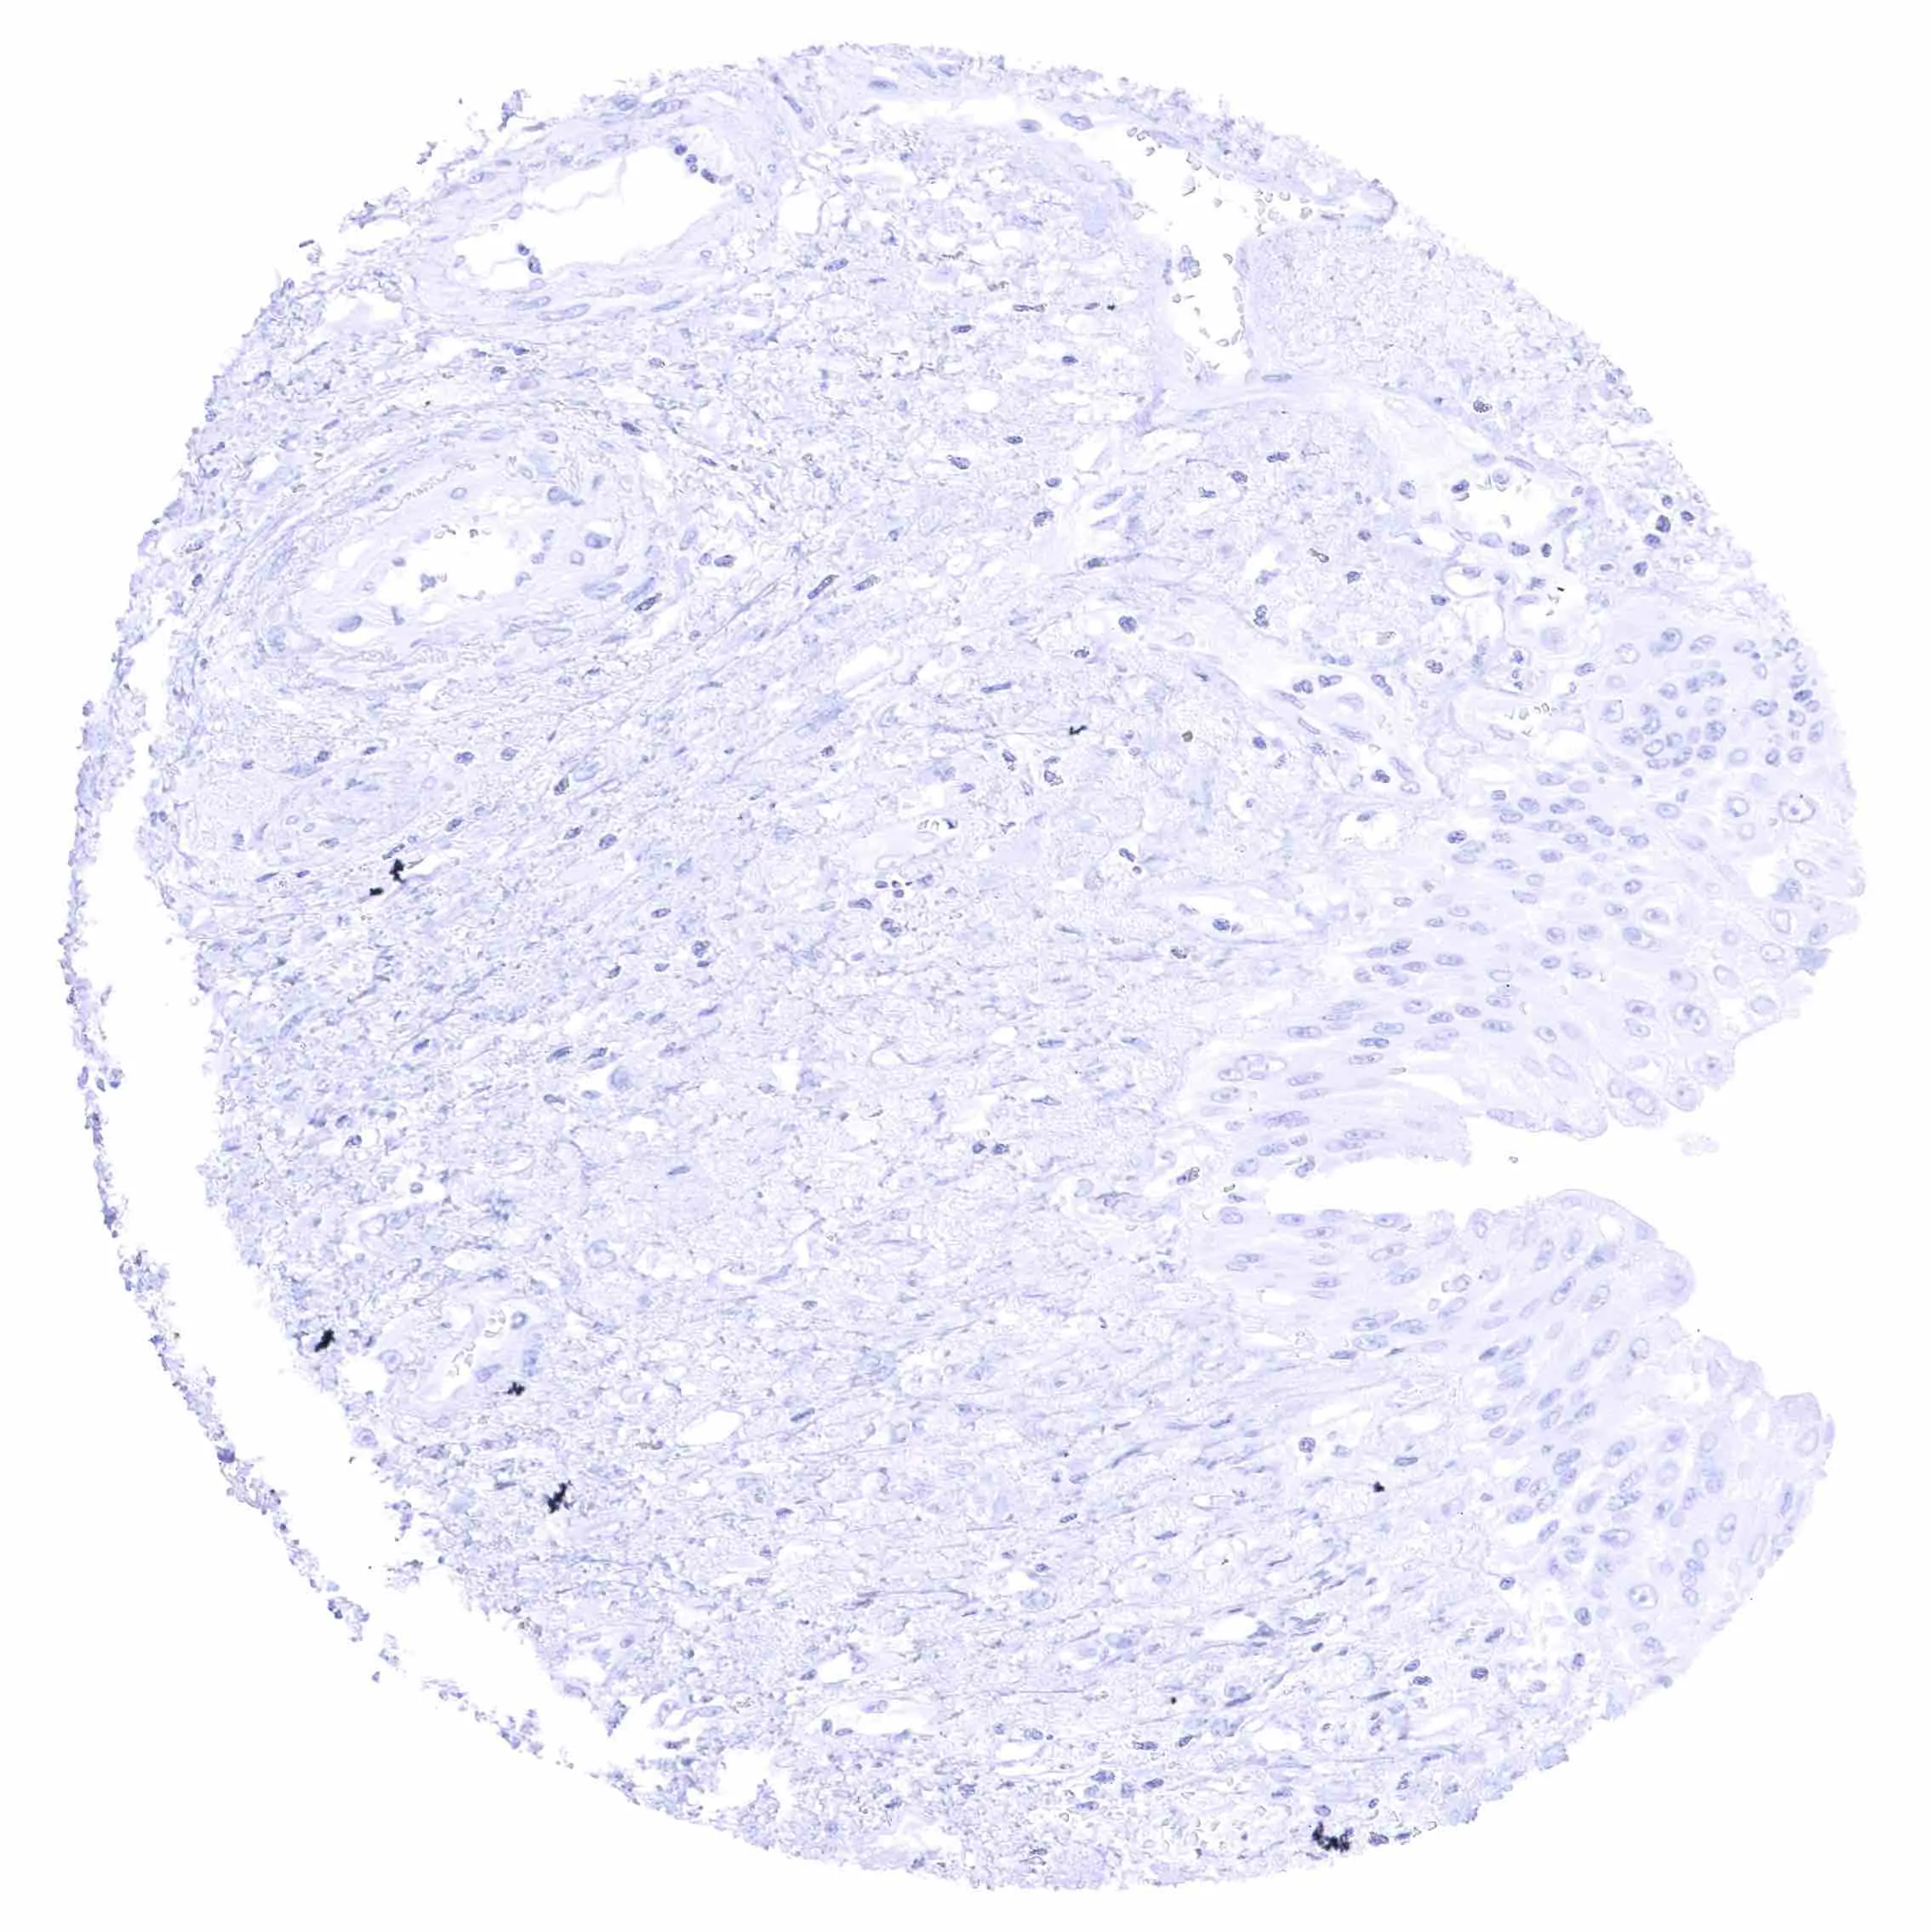

Skin